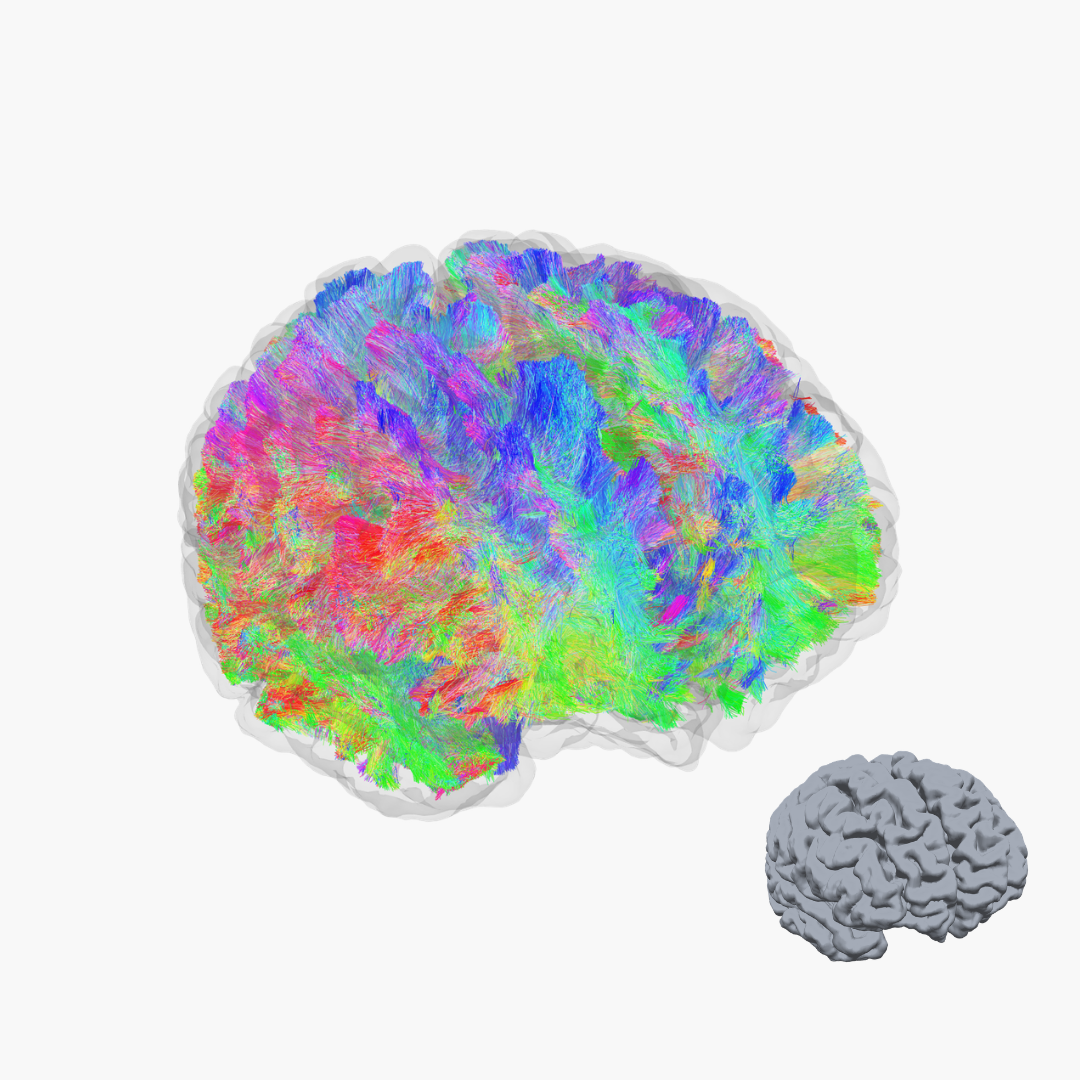

Strukturelle Analyse

Die strukturelle MRT und Traktographie machen die feinen Nervenfaserbahnen (weiße Substanz) sichtbar, die für eine gesunde Funktion des Gehirns entscheidend sind.